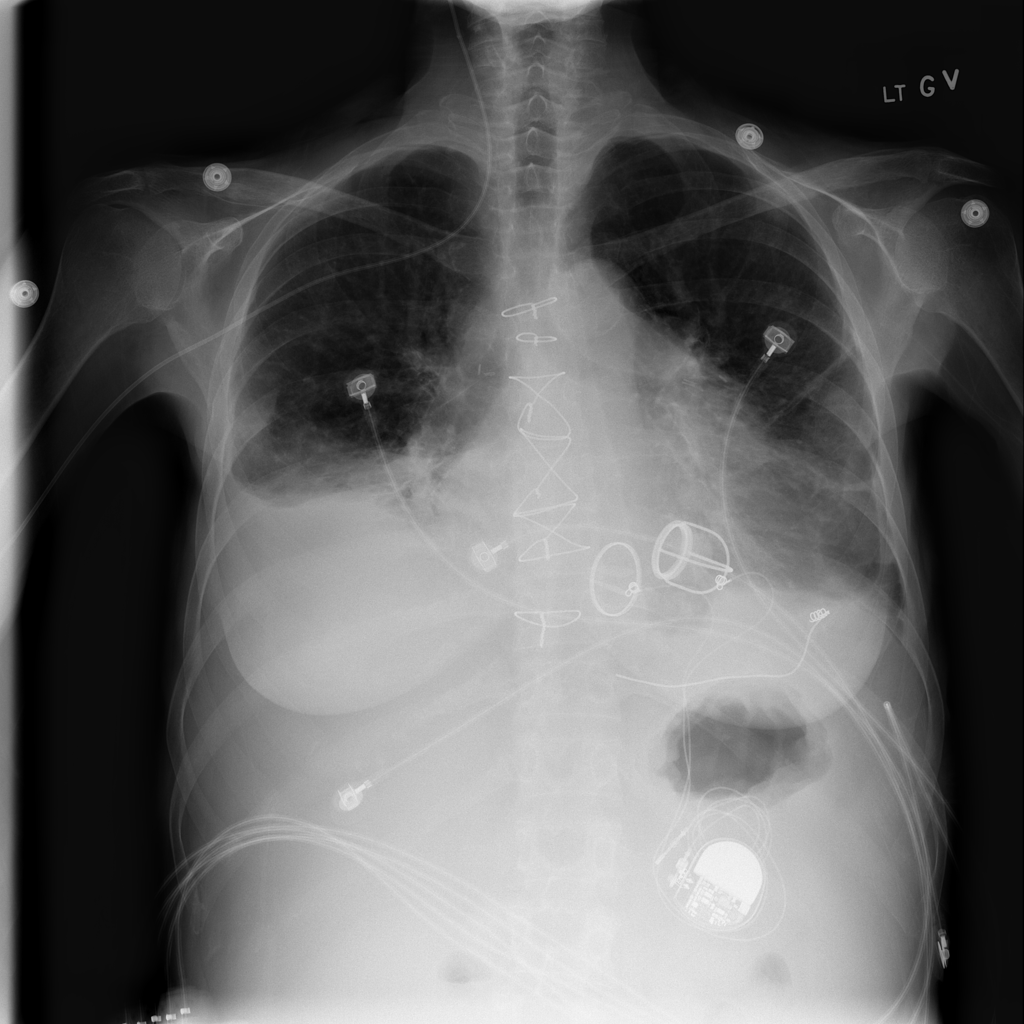

PAT-C0E5 · IMG-006Effusion

PAT-C0E5 · IMG-006

AP